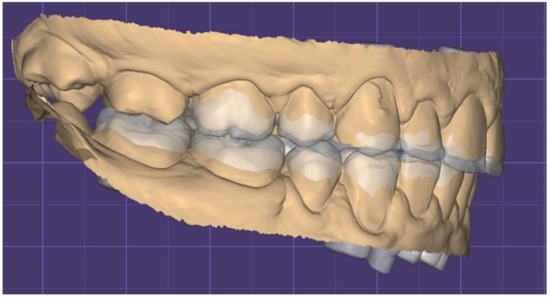

2.1. Planning Phase